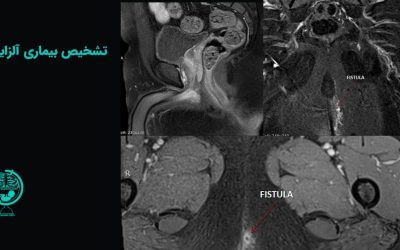

تشخیص بیماری آلزایمر با بهترین روش ها

یکی از بیماریهای شایع در میان سالمندان آلزایمر است که عموم مردم آن را با از دست دادن حافظه میشناسند. در اغلب موارد این بیماری در سنین سالمندی بروز پیدا میکند. مانند تمام بیماریها، تشخیص بیماری آلزایمر در زمان مناسب، بابت انتخاب روشهای درمانی بسیار کمک کننده است.